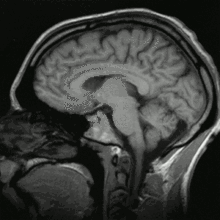

متلازمة الألم المركزية، هي حالة عصبية عضوية سببها الرئيسي عطل النظام العصبي المركزي (سي إن إس) central nervous system (CNS)، الذي يتضمّن الدماغ، النخاع، والحبل الشوكي.[1][2][3]